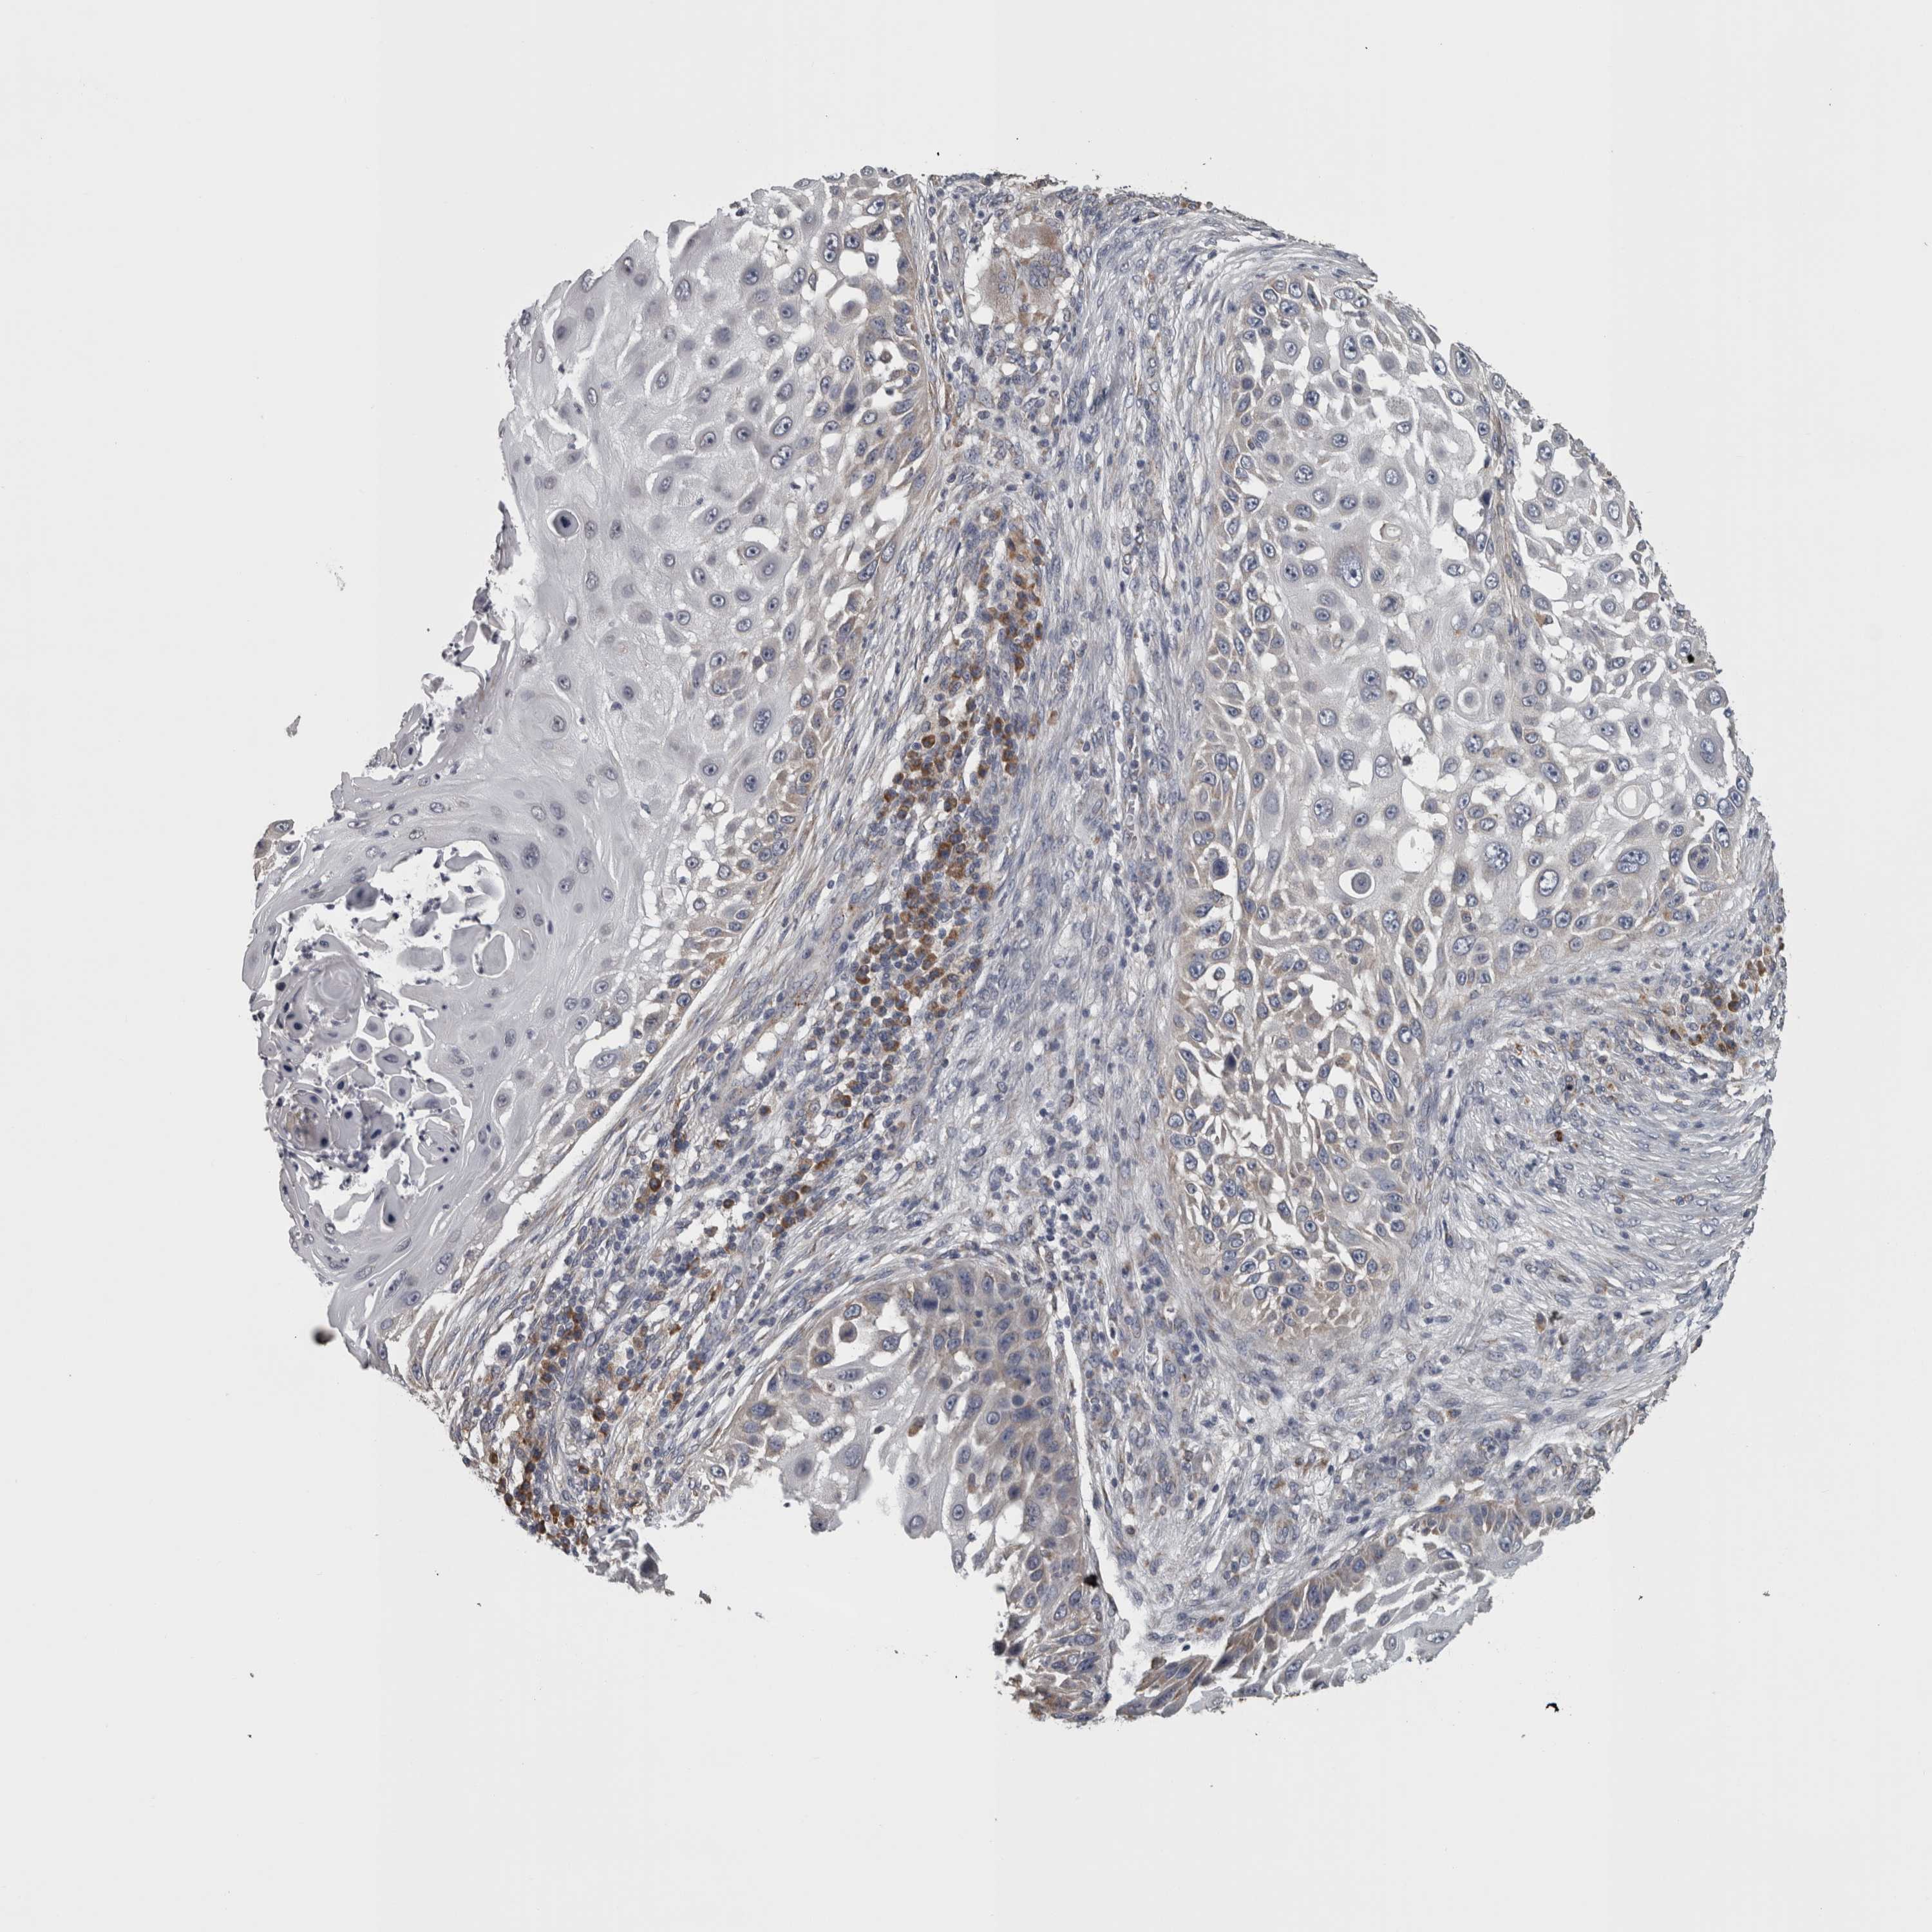

SKIN CANCER - Protein expressioni

A mouse-over function shows sample information and annotation data. Click on an image to view it in a full screen mode. Samples can be filtered based on level of antibody staining by selecting one or several of the following categories: high, medium, low and not detected. The assay and annotation is described here.

Antibody stainingi

Antibody staining in the annotated cell types in the current human tissue is reported as not detected, low, medium, or high, based on conventional immunohistochemistry profiling in selected tissues. This score is based on the combination of the staining intensity and fraction of stained cells.

Each image is clickable and will lead to virtual microscopy that enables deeper exploration of all samples and also displays staining intensity scores, fraction scores and subcellular localization as well as patient and tissue information for each sample.

Antibody HPA072590

Basal cell carcinoma